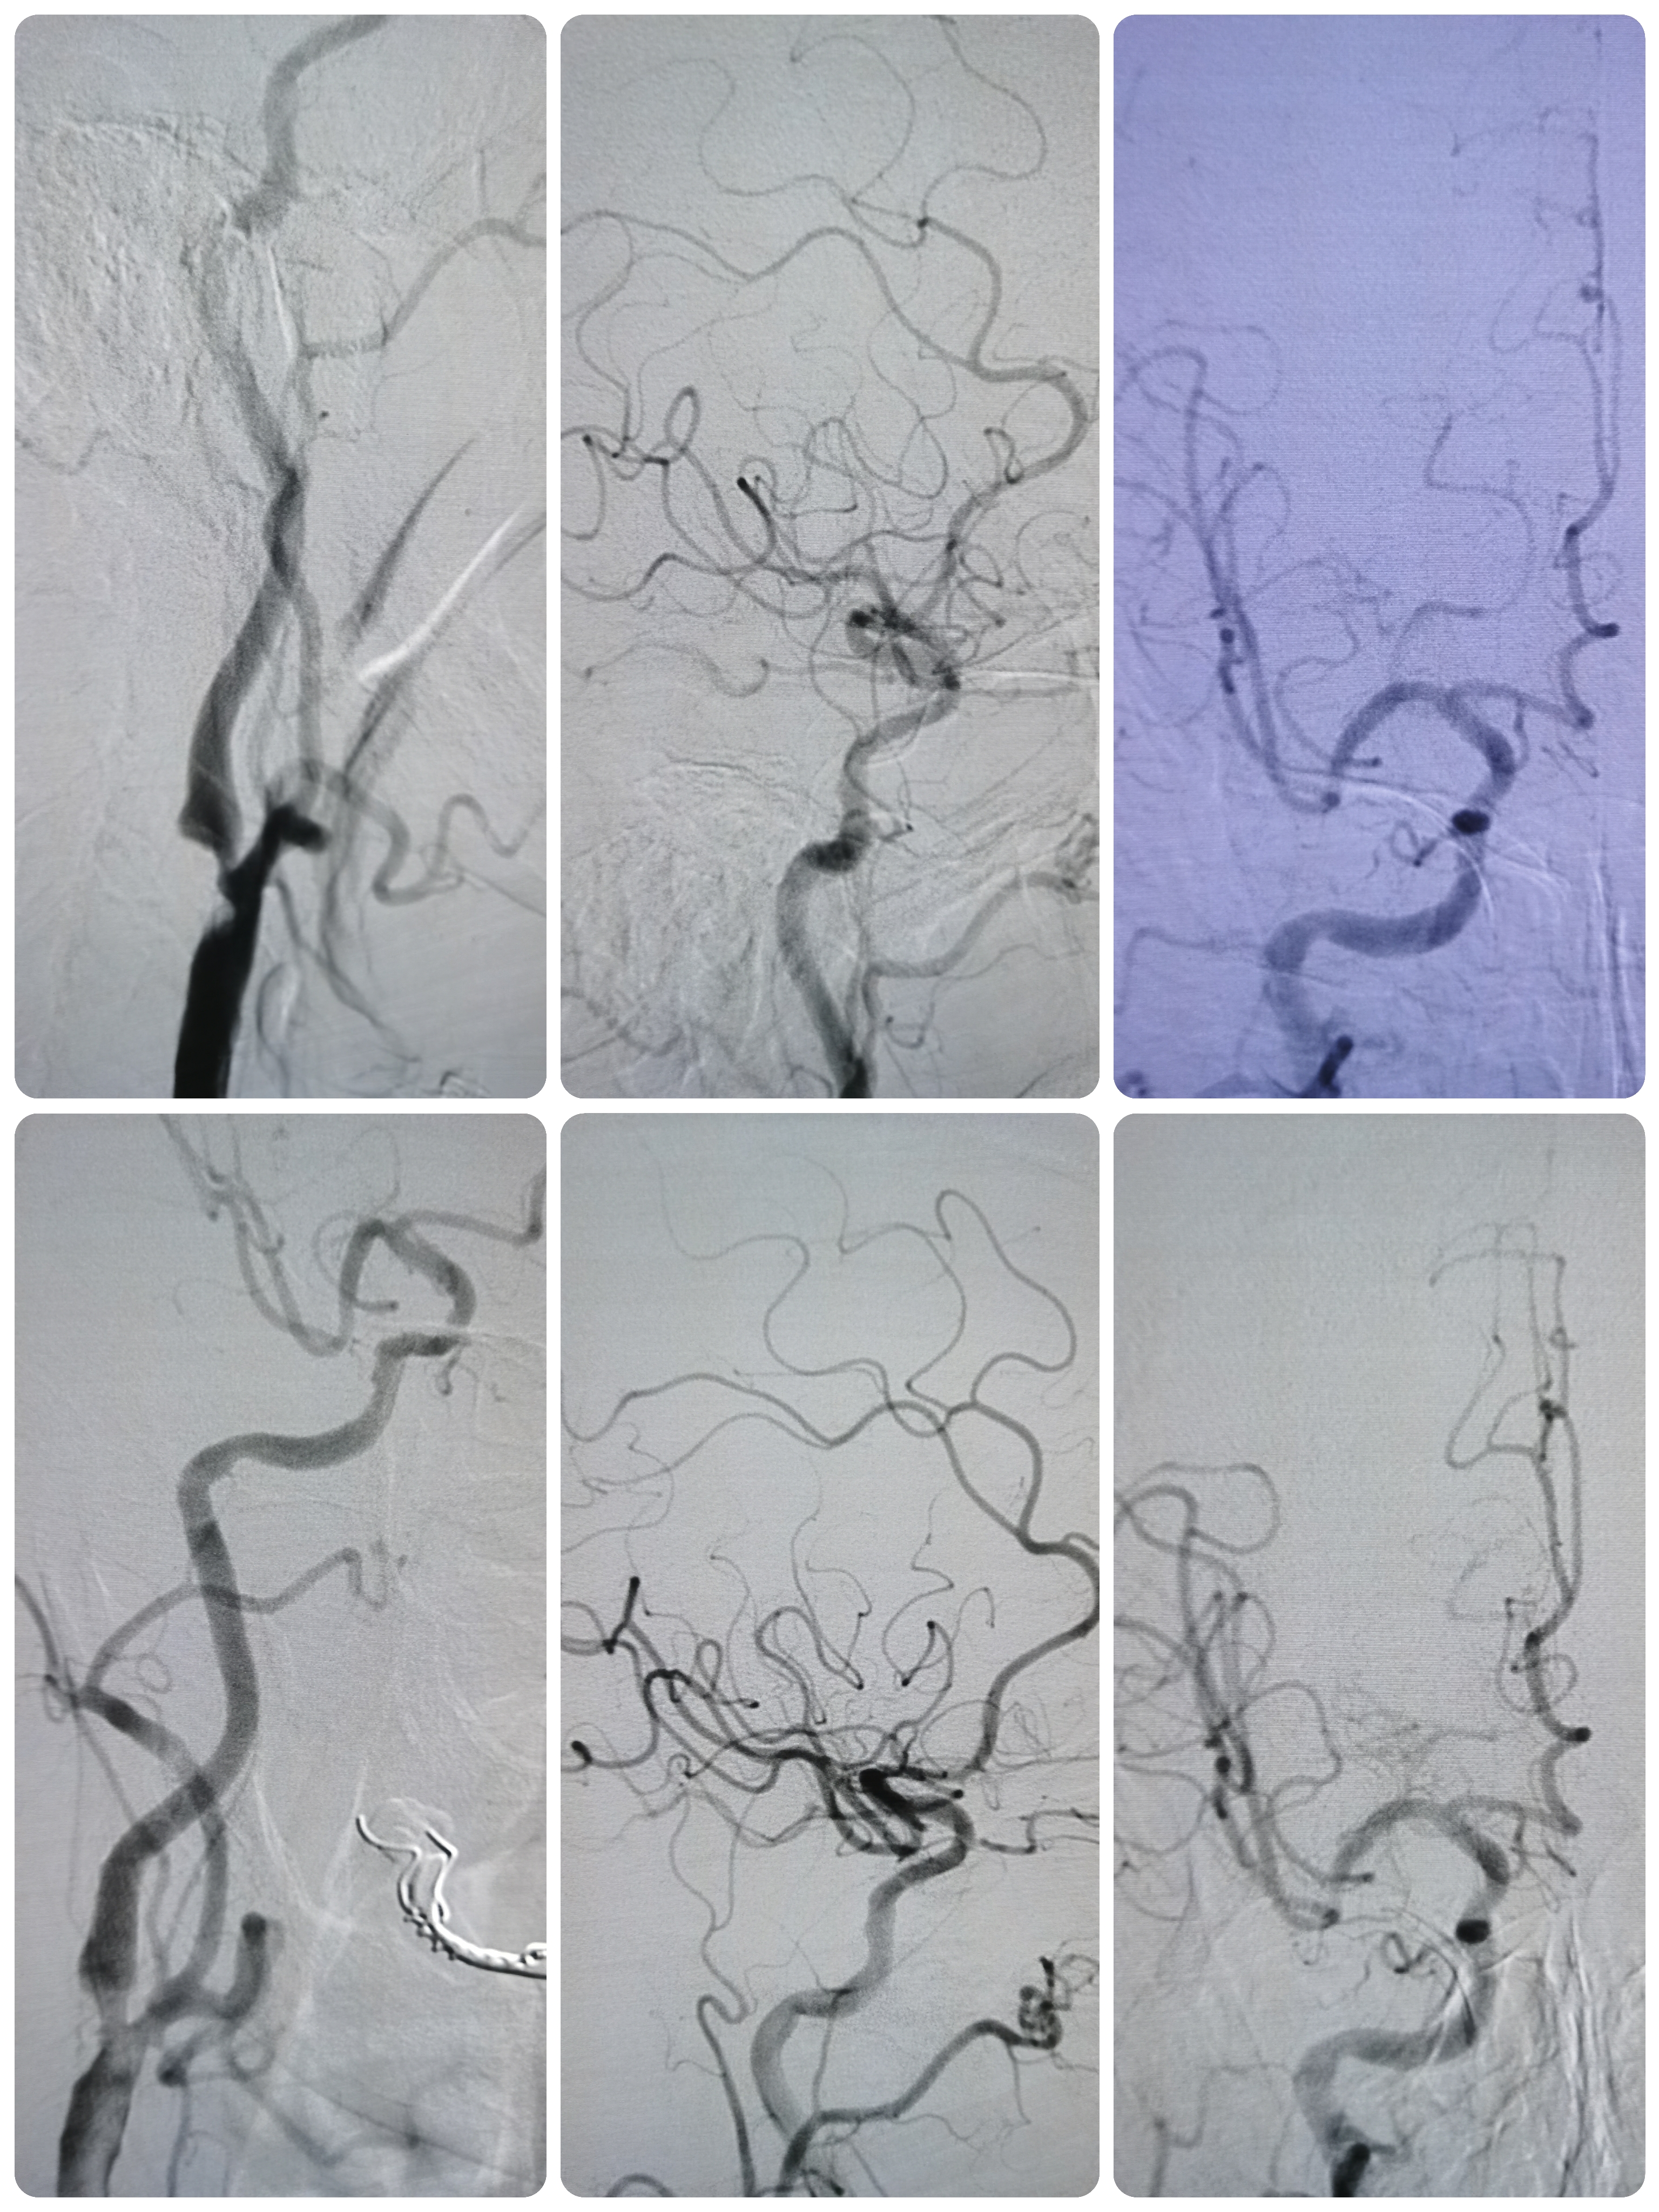

DSA示右椎动脉优势,起始部极重度狭窄,左侧椎动脉完全反向血流,动脉晚期可见左侧锁骨下动脉闭塞端。

右椎动脉起始部极重度狭窄。

右颈内动脉窦部重度狭窄,局部斑块不稳定。

右颈颅内段动脉硬化,右侧后交通动脉开放。

左侧颈内动脉起始部粥样硬化斑块,狭窄50%。

左侧锁骨下动脉起始部完全闭塞。

1、造影明确左侧锁骨下动脉起始部完全闭塞,右椎造影可见左椎返流,晚期可见圆钝的锁骨下动脉闭塞端,结合病史考虑闭塞时间较长。

2、右椎动脉起始部极重度狭窄,系责任血管。

3、右侧颈内动脉起始部重度狭窄,局部斑块不稳定,且右侧后交通动脉开放。

5.0/15支架定位

支架释放后狭窄解除

将导引导管调至右侧颈总末端,送入远端保护伞,4/30球囊预扩。

7-9/40支架定位

支架释放后狭窄改善,考虑患者高龄,颅内动脉硬化,担心术后高灌注出血,遂未再进行大球囊后扩。

撤出保护伞,造影见狭窄改善明显。

术前术后对比